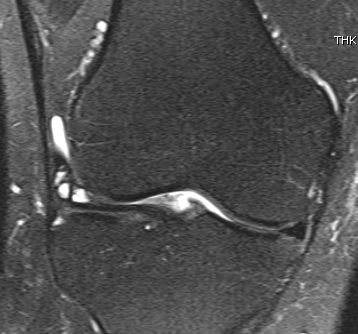

MRI

Meniscal tear + associated lateral meniscal cyst